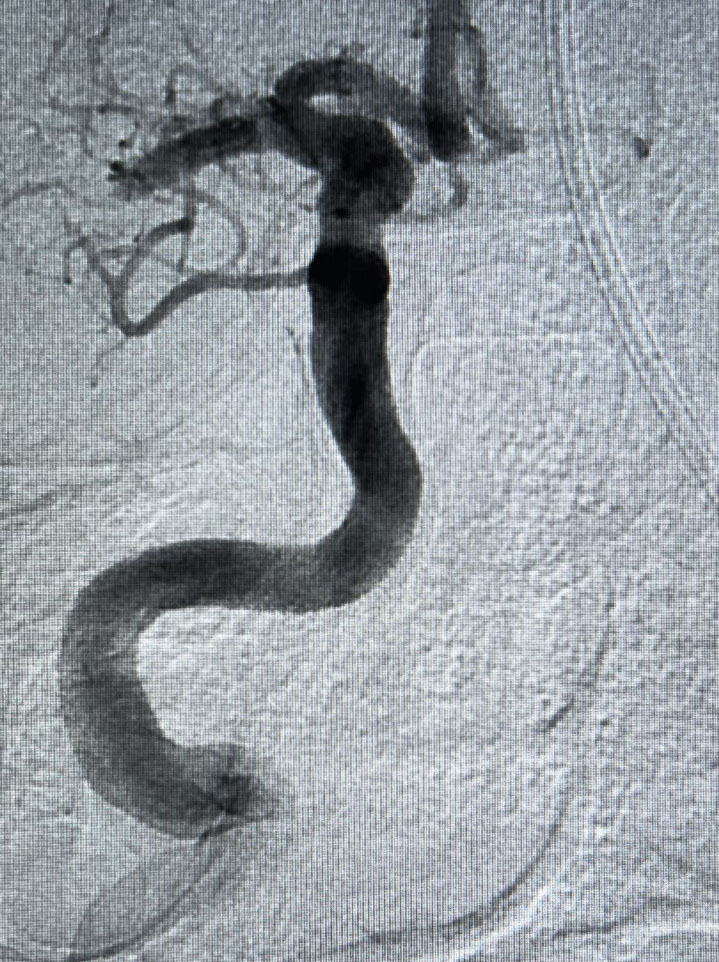

Then Ron was flighted to Banner Wyoming Medical Center.  When he arrived, Dr. Wheeler along with interventional radiologist Eric Cubin, M.D., determined that Ron’s stroke was not yet complete and that he was a good candidate for mechanical clot retrieval. Interventional radiologists make this type of stroke treatment possible at Banner Wyoming Medical Center.  Fellow interventional radiologist Ryan Bonifield, D.O., came over to perform the procedure.

Fortunately for Ron, Banner Wyoming Medical Center’s multidisciplinary team is experienced in springing into action for severe strokes such as the one he suffered. Inside the interventional radiology suite, Dr. Bonifield accessed the common femoral artery near Ron’s groin and inserted a small guide wire covered with a vascular sheath. Guided by real-time X-ray imaging, Dr. Bonifield snaked the guide wire through Ron’s arteries and around a complex path to the artery in his neck. He then passed smaller tubes into the blocked artery in Ron’s brain and released a special device to grab the clot and remove it. After three passes, he retrieved the clot and restored blood flow to Ron’s brain.